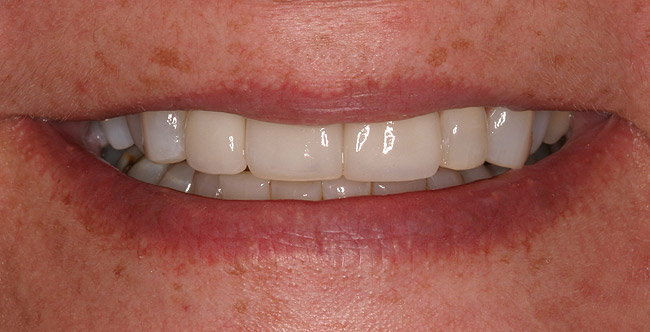

Figure 7a  Recently extracted tooth No. 9 (upper left central incisor), grafted site. Heavily treated adjacent teeth Nos. 8 and 10 with three-quarter porcelain laminate veneers.

Figure 7a

Figure 7b  Recently extracted tooth No. 9 (upper left central incisor), grafted site. Heavily treated adjacent teeth Nos. 8 and 10 with three-quarter porcelain laminate veneers.

Figure 7b

Figure 7c  Completed single all-ceramic screw-retained implant crown site on tooth No. 9, revised porcelain three-quarter laminate veneers for teeth Nos. 8 and 9, cemented with Kerr NX3 Nexus¬Æ Third Generation Dual Cure Resin cement.

Figure 7c

Figure 7d  Completed single all-ceramic screw-retained implant crown site on tooth No. 9, revised porcelain three-quarter laminate veneers for teeth Nos. 8 and 9, cemented with Kerr NX3 Nexus¬Æ Third Generation Dual Cure Resin cement.

Figure 7d

Figure 7e  Completed single all-ceramic screw-retained implant crown site on tooth No. 9, revised porcelain three-quarter laminate veneers for teeth Nos. 8 and 9, cemented with Kerr NX3 Nexus¬Æ Third Generation Dual Cure Resin cement.

Figure 7e

When a patient presents with a missing anterior tooth and heavily treated adjacent teeth, although conceptually an FPD option may seem the most appropriate choice, it can be argued that it would not be the most favorable option. If long-term treatment outcome is a strong motivator for the patient, then a treatment plan that includes individual restored units would be the more appropriate choice. Consequently, the patient would most likely have improved benefit with a single implant-supported restoration and treating the adjacent teeth as separate, single units (Figure 7).